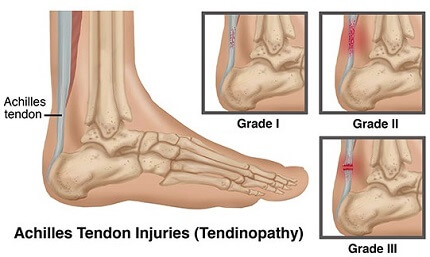

Ease the ache of Achilles tendinitis clearance, Forefront healthcare Achilles Tendonitis Treatment foot problem treatment in India. Achilles tendonitis may be felt as a burning pain at the beginning of an Instagram clearance, Foot and Ankle Pain clearance, Achilles Tendon Ruptures SpringerLink clearance, Burning Pain After Achilles Tendon Surgery Excel PTExcel Sports PT clearance, Achilles Tendonitis Symptoms and Causes Penn Medicine clearance, Upper Heel Pain Causes and Treatment Sydney Heel Pain clearance, Foot Ankle Tendonitis Podiatrist NYC Downtown Step Up Footcare clearance, Happy Walker Your Foot Solution Blog Achilles Tendonitis clearance, 3 STEP DIAGNOSIS Achilles Tendinitis Zlaant clearance, What to Do When Your Heels Are on Fire clearance, Sharp Pain in the Achilles Tendon Causes Best Treatment clearance, The Achilles Tendon Clinique du pied Achilles tendon clearance, Achilles Tendon Injury Baltimore MD International Center for Limb Lengthening clearance, Pain at the back of the heel How to figure out what s causing it and what to do about it clearance, Achilles Tendonitis and Tears DocMartins Foot Ankle Clinics clearance, Achilles Tendon Rupture Rehabilitation Frank Gilroy Physiotherapy clearance, Rare association of thermal burns of the knee and ankle with wounds of the patellar and achilles tendons ScienceDirect clearance, What Is Enthesitis Causes Symptoms Treatments clearance, Achilles Tendinopathy NHS Lanarkshire clearance, Heel Pain Causes Treatment and Prevention clearance, Achilles Tendonitis Treatment Recovery Foot Pain Explored clearance, Achilles Tendonitis Orange County Orthopedic Center clearance, Achilles Tendonitis Treatment Recovery Foot Pain Explored clearance, Achilles Tendon Tear Symptoms Causes clearance, The Achilles Tendon Clinique du pied Achilles tendon clearance, Achilles tendonitis symptoms causes and diagnosis clearance, How to Treat Achilles Tendon Pain Foot and Ankle Group clearance, Tarsal Tunnel Syndrome Burning and Numbness Heel clearance, Tendinopathy Symptoms Causes Treatment clearance, Pain and Burning in the Achilles Tendon clearance, Achilles Tendonitis Treatment in Melbourne Achilles Tendon Pain clearance, The Signs of Achilles Tendinitis Sydney Heel Pain clearance, Achilles Tendonitis Orange County Orthopedic Center clearance, Why You Should Never Ignore Achilles Heel Painv Suncoast Orthopaedic Institute clearance, Product Info: Achilles tendon burns clearance.

Achilles Tendon Rupture Rehabilitation Frank Gilroy Physiotherapy- achilles tendon burns

- achilles tendon bursitis causes

- achilles tendon bursitis symptoms

- achilles tendon bursitis treatment

- achilles tendon calcaneus pain